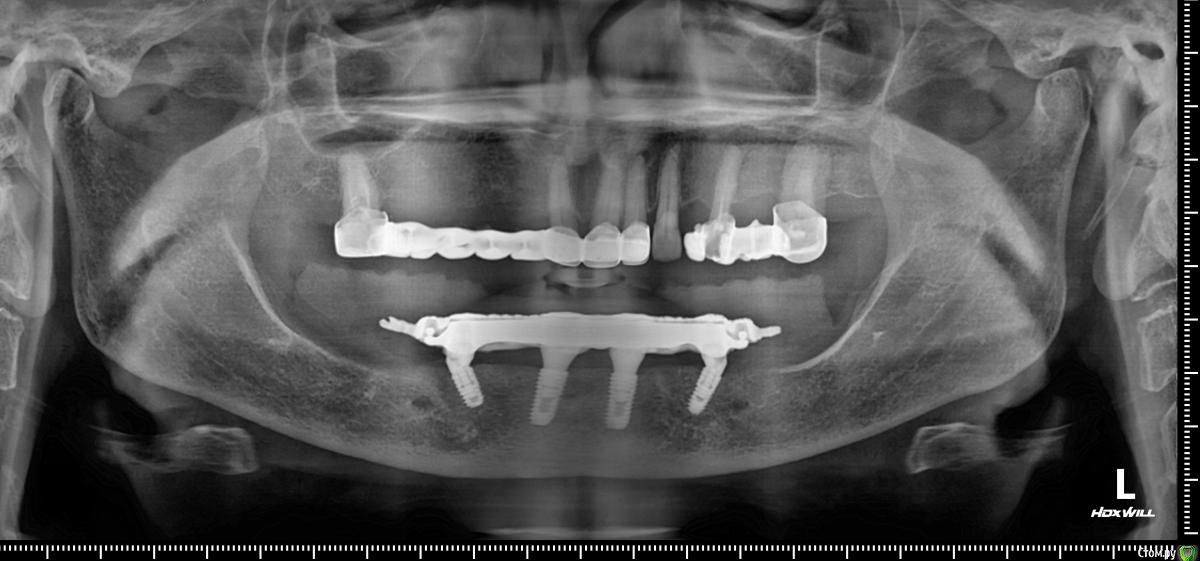

Панорама post-36568-0-16435400-1566455538_thumb.jpg как будто дистально балка прилегает хуже, но все держится без втулок. Пока что делать ничего не буду, понаблюдаем.